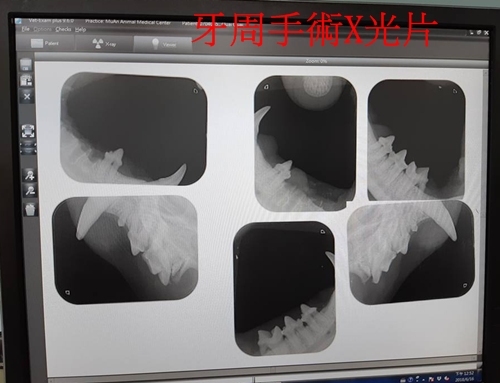

牙周手術 沐恩

體重:4.895kg

醫師說明

拐拐的口炎很嚴重,有增生組織,通常口炎嚴重的貓咪多數會建議後面臼齒全拔,但因照X光結果除了最後一顆牙之外其他牙根都很好,所以今天沒有全拔,主要是處理口腔後段部份的牙齒,中段之前的牙都還留著。

上下各留一顆小的臼齒讓牠可以叼食物,但用來咬碎就比較沒辦法,主要用來咬碎的大臼齒,下方拔兩顆只留一顆,因為若留下並排的牙,有牙縫容易有細菌怕再發炎,下方兩顆大臼齒因離發炎處近所以就全拔掉,有一側因為較難拔有剝開牙齦再縫合。